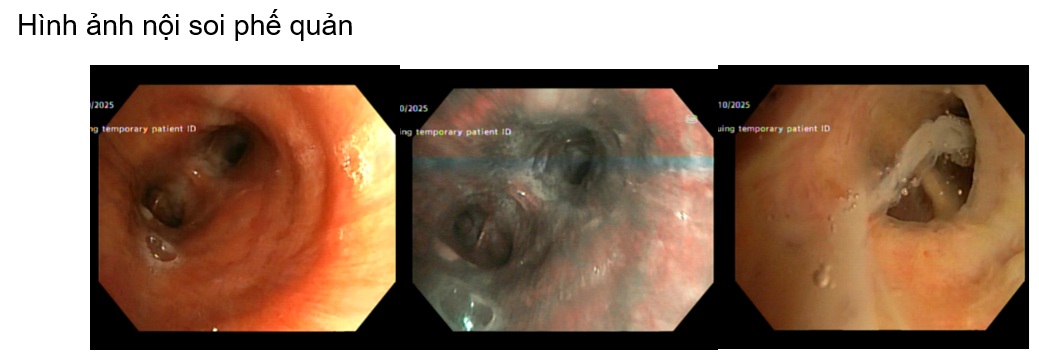

Một trường hợp lâm sàng tại khoa Nội tổng hợp, bệnh nhân nam L.V.R 80 tuổi, vào viện vì sốt, tiêu lỏng kèm khó thở, nặng ngực. Tiền sử tăng huyết áp, chưa ghi nhân bệnh lý hô hấp, bệnh mạn tính khác trước đó. Bệnh nhân nhập viện với tình trạng nhiễm trùng nhiễm độc, tổn thương thận cấp. Trong quá trình nằm viện bệnh nhân khó thở tăng dần suy hô hấp, sốt cao dao động 39 – 400C, đáp ứng kém với phác đồ kháng sinh ban đầu (piperacillin/tazobactam + levofloxacin). Bệnh nhân được nội soi phế quản, sau 5 ngày nhập viện kết quả cấy dịch rửa phế quản Candida albican, bệnh nhân được chỉ định phối hợp sử dụng kháng nấm anidulafungin. Sau 4 ngày sử dụng kháng nấm, lâm sàng bệnh nhân cải thiện hết sốt, ngưng được oxy, thở đều êm, chức năng thận hồi phục.